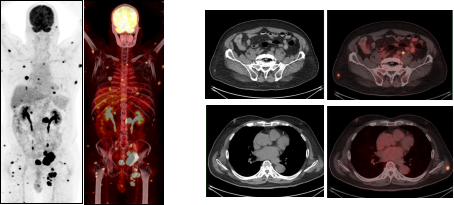

3.4肿瘤分期对比

图A 图B

A、B两图均为左肺周围型肺癌,病灶大小相似,A未见远处转移病灶,B全身广泛转移,临床分期分别为ⅡB期及ⅣB期,PET/CT不同分期影响临床治疗决策。